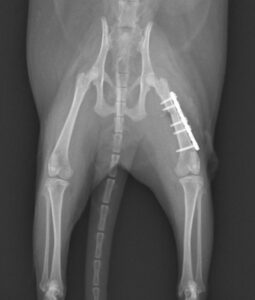

大腿骨骨折のフェレットちゃんの手術依頼でご紹介がありました。TAITAN1.2プレートを使用し無事歩けるようになりました。よかったね。